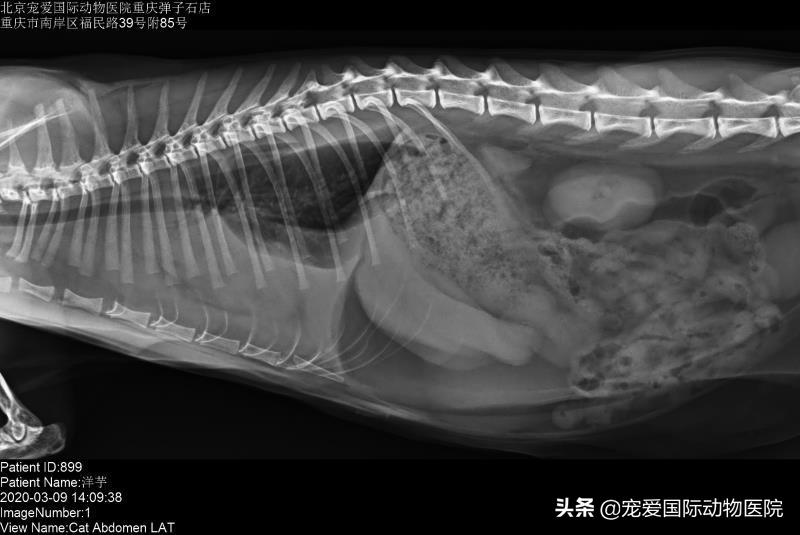

DR显示有胸水

经过一周治疗,洋芋呼吸情况明显好转,食欲恢复正常,精神良好,排便情况正常,复查x光胸水逐步在减少,肺叶逐渐恢复正常。继续用药到3周复查,胸水消失,各项指标恢复正常。整体治疗效果良好,遂出院。

治疗第二周,胸水逐步减少,呼吸趋于平稳。